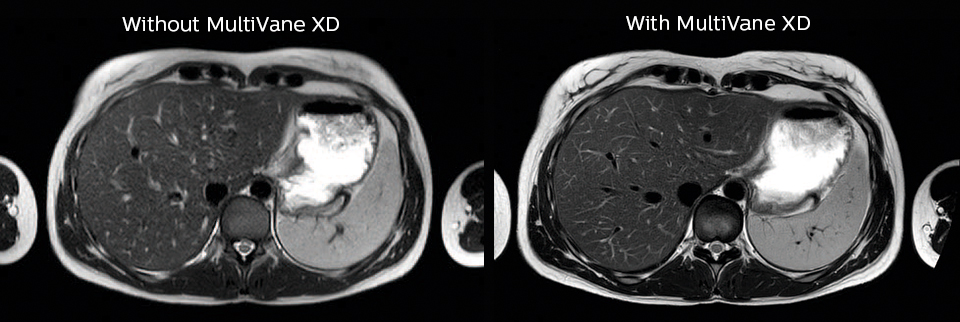

Motion reduction

“We also love MultiVane XD for motion reduction in imaging.

We find this a huge step forward. We use it in the head, and of course in the upper abdomen, and the images are outstanding most of the time. And it can be combined with dS SENSE parallel imaging for speed.”

“We have compared image quality of FLAIR with MultiVane XD versus FLAIR without MultiVane XD. In 15 of the 40 patients studied, we saw motion artifacts on plain FLAIR brain images. The FLAIR images with MultiVane XD were motion-free in 39 of 40 patients and showed slight motion artifacts in only one patient.”